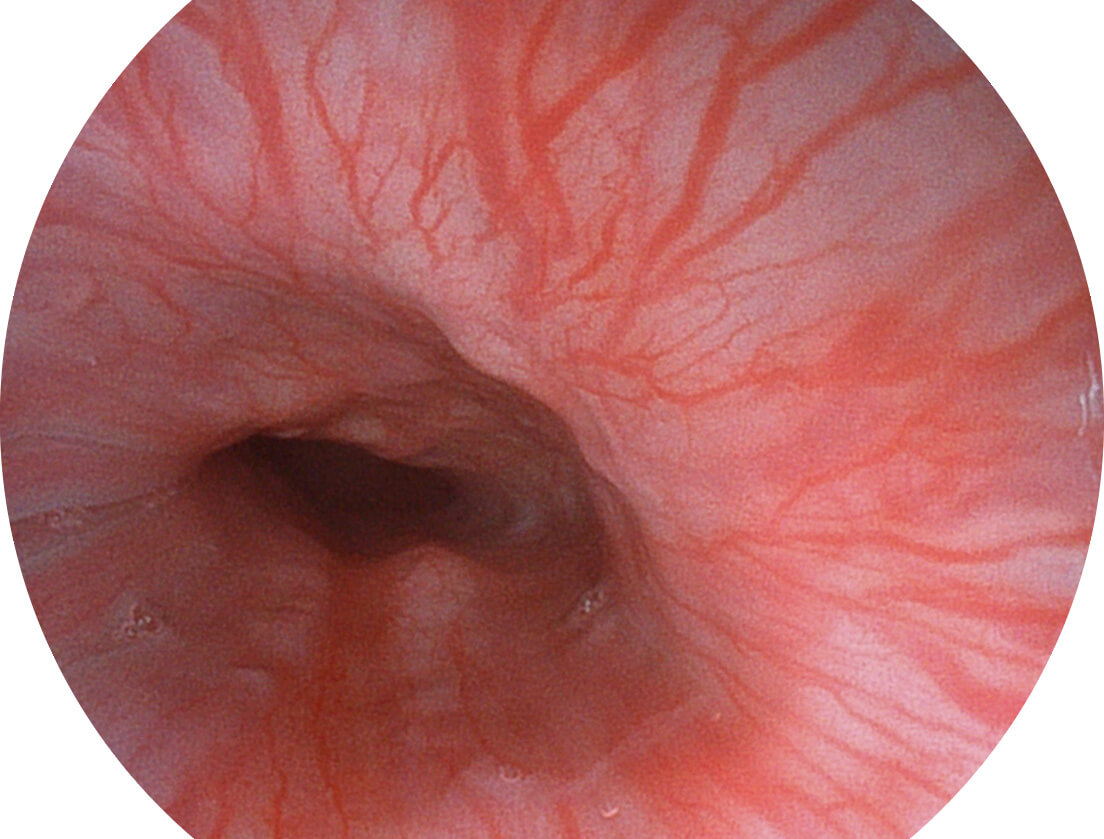

采用无损耗高清数字接口,视频输出分辨率≥1920×1080,图像清晰、细腻。

采用光路合束技术,光谱自由度高,实现了更丰富的照明模式,染色模式SFI及VIST,从远景到近景,助力消化道早期疾病诊断。